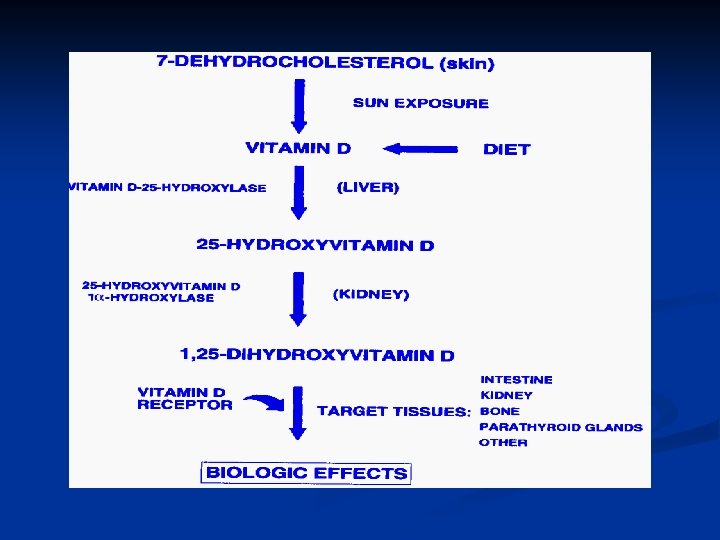

Biochemistry of Vitamin D 3 – Brief Review Vitamin D 3 (cholecalciferol) is synthesized in the skin, with UV light, from 7 -dehydrocholesterol n Vitamin D 3 is hydroxylated twice – first in the liver, to 25 hydroxycholecalciferol, then in the kidney, to 1, 25 dihydroxycholecalciferol, the most potent form of Vitamin D n

Vitamin D metabolism

Vitamin D Metabolism

Vitamin D (cont’) n Primary role of Vitamin D n n Increase calcium and phosphate absorption from the intestines Other tissues that Vitamin D acts on Parathyroid glands n Bone, Kidneys n Skin, Brain, Pituitary n Lymphocytes, Tumors n